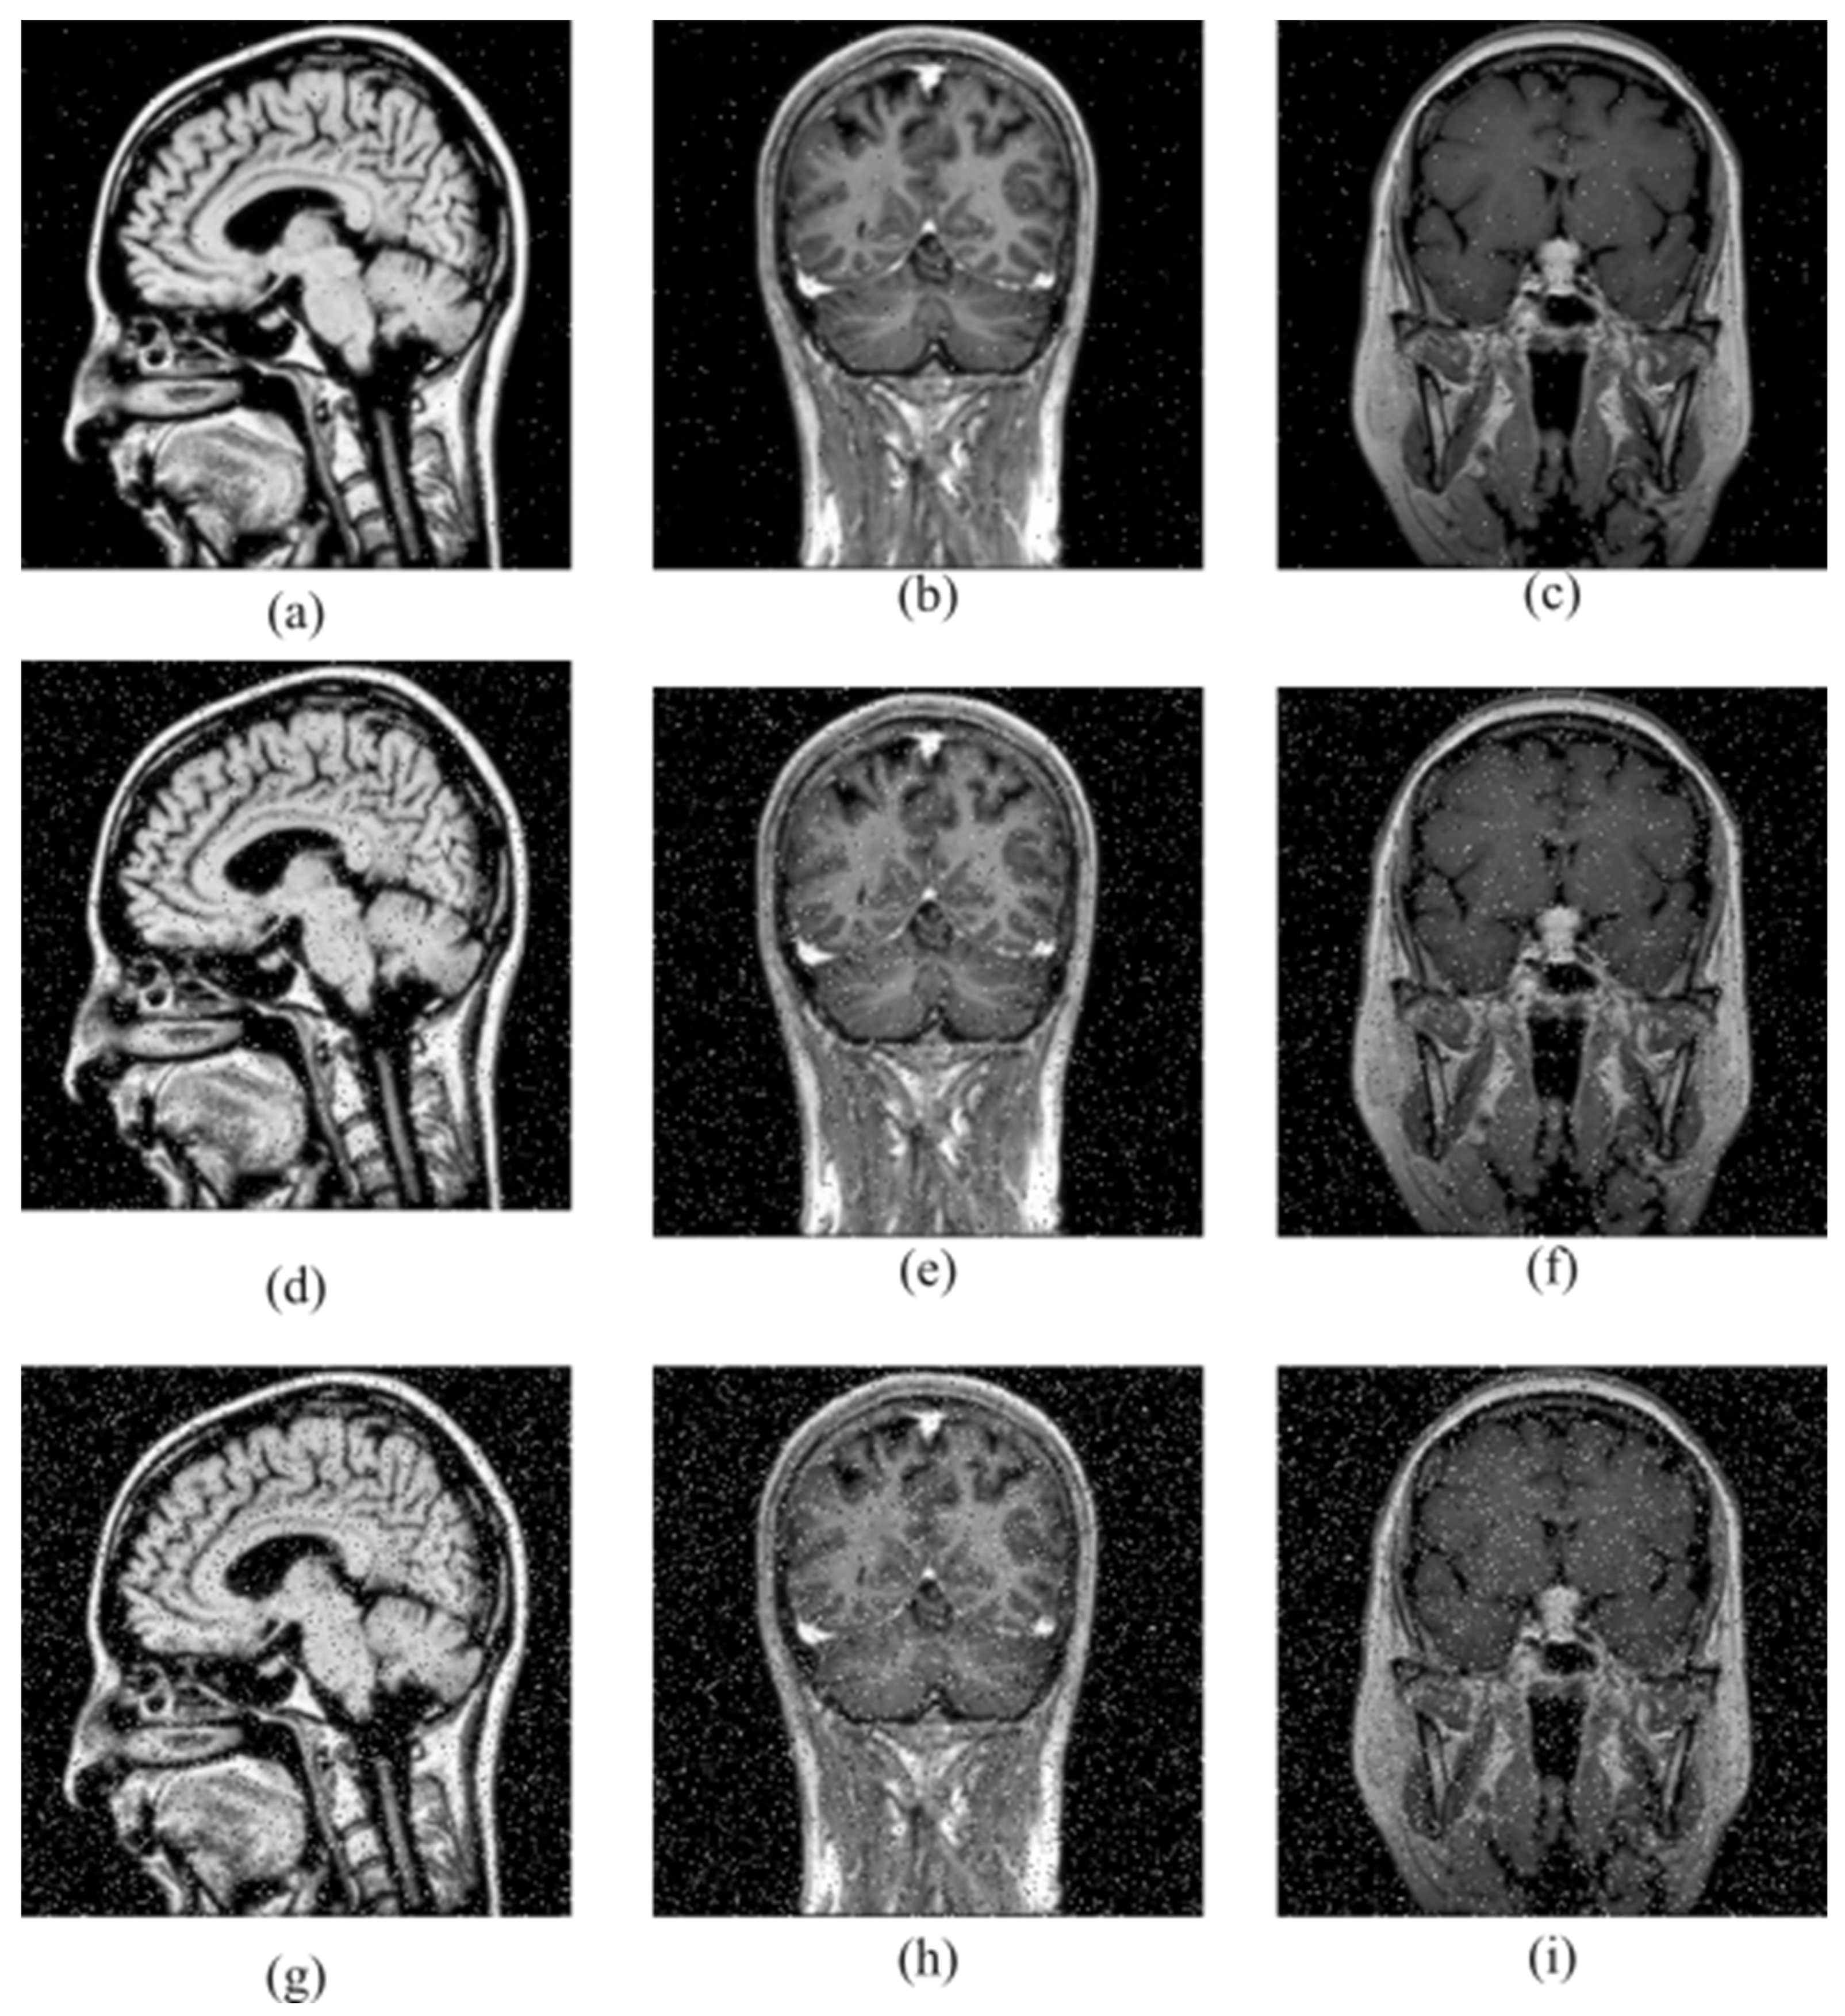

Various forms of noise in the communication channel often affect encrypted images. A good encryption system should be able to successfully recover the source image from the noisy encrypted image. In our work, salt-and-pepper noises of different intensities are added to the encrypted image to measure the robustness against noise. Decryption was then performed. The results are shown in Figure 8. Table 9 shows the PSNR values obtained as a result of salt-and-pepper noise attacks.

Figure 8.

Decryption images under salt-and-pepper noises of different intensities: (a–c) intensity is 0.01, (d–f) intensity is 0.05, (g–i) intensity is 0.1.

Table 9.

PSNR value of images obtained as a result of salt-and-pepper noises.

According to the obtained results, it is clear that the source image can be successfully restored even if the encrypted images are subjected to noise. Therefore, it is seen that the proposed method is robust against noise attacks.